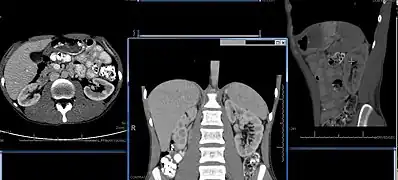

Imaging

Renal ultrasonography is essential in the diagnosis and management of kidney-related diseases.[46] Other modalities, such as CT and MRI, should always be considered as supplementary imaging modalities in the assessment of renal disease.[46]